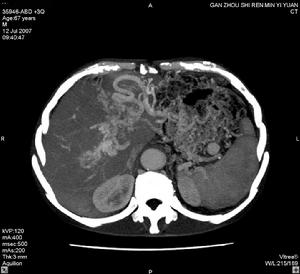

門脈病變

門脈高壓性腸病肝硬化的發生,其病變嚴重程度與門脈高壓程度成正比。一直以來,臨床上多把肝硬化、肝癌並發上消化道出血歸咎於食管靜脈曲張破裂出血,而事實上,門脈高壓性胃病及肝源性潰瘍則是另一類不容忽視的主要病因之一。據一項統計顯示,在肝硬化門靜脈高壓合併上消化道出血的病例中,食管靜脈曲張破裂出血占48.11%,門脈高壓性胃病及肝源性潰瘍所致的出血占28.16%,而近年來門脈高壓性腸黏膜病變出血也不在少數。由於當時出血原因不明,出血後門脈壓以及局部血管張力下降,局部血管收縮,出血點迅速閉合,以至於之後的胃腸鏡檢查中找不到出血點,造成診斷的困難。